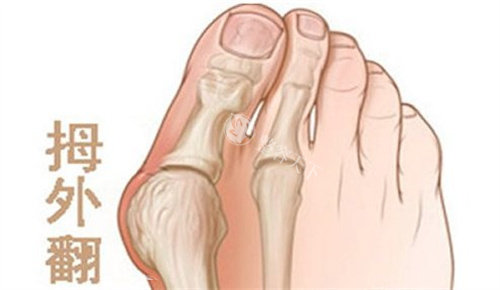

困扰多年的双脚难题

我的双脚大脚趾根部长期以来一直向外突出,形成难看的骨凸。不仅穿鞋经常磨脚,走路时间稍长就会隐隐作痛。每到夏天,我总是避免穿凉鞋,担心别人看到我变形脚型的异样眼光。这种困扰像块沉甸甸的石头压在我的心头,让我渴望找到解决之道。

接诊的医生经验充足且态度和蔼。他仔细检查了我的双脚,让我做了一些简单动作来观察脚部活动情况,还结合X光片详细解释了拇外翻的形成原因和发展程度。这种正规的讲解让我对自己的病情有了清晰认识,也对后续治疗增添了信心。

医院采用的小创口技术切口很小,只有3-5毫米,通过这种微小切口就能祛除骨赘。手术结合了更准矫正和牵引技术,避免了传统截骨手术的一些风险。据了解,这种技术术后24小时就能下地行走,复发率也控制在很低水平。